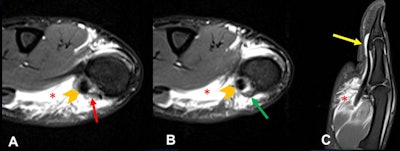

Thumb pulley injury. A 17-year-old male goalkeeper with pain after trauma on the thumb. (A, B) axial and (C) sagittal T2-weighted fat-suppressed images show thickening and irregularity of the A1 pulley (red arrow) and annular pulley or Av pulley (green arrow). Tenosynovitis of the flexor pollicis longus is visible (yellow arrow) with tendon integrity (orange chevron). Moderate diffused edema of the thenar muscles, surrounded with some fluid, related to the contusion (red asterisks), is also demonstrated.MCP and CMC fractures tend to be stable due to the lower energy of sports-related injuries. Casting or splinting is recommended, with return to sport in between two and eight weeks. Malrotation or an unstable fracture requires closed reduction percutaneous pin fixation or open reduction internal fixation.